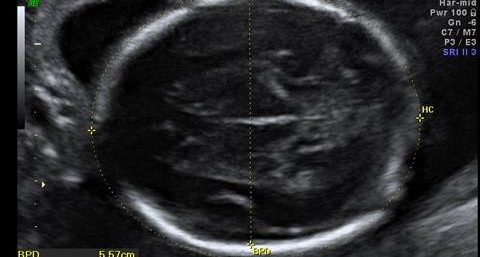

Ultrassom Polo Cefálico

Intervalos de Referência das Medidas do Diâmetro Biparietal (DBP), da…

Médicos, Tabelas

12/09/2014   72296 Views

As tabelas aqui descritas são denominadas de tabelas de valores de REFERÊNCIA. Valores acima ou abaixo dos limites esperados NÃO…

Polo Cefálico

Tabelas

20/02/2011   15372 Views

Veja abaixo as principais tabelas de medidas do polo cefálico fetal realizadas ao ultrassom: Intervalos de Referência das Medidas do…